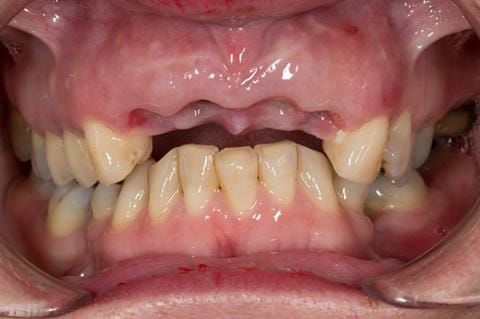

- UR2 peri-radicular periodontitis with a peri-radicular area on the root apex. Retrograde amalgam filling from a previous apicectomy. No visible root canal or root canal filling. Large circumferential marginal gap between the crown and tooth. Large post and core present. Very little tooth structure remaining resulting in a fragile tooth with increased potential for fracture.

- UR1 peri-radicular periodontitis with a small peri-radicular area on the root apex with wide blunderbuss apex. Radio-opaque root canal filling present approximately 3 mm short of the radiographic apex. Large circumferential marginal gap between the crown and tooth. Large post and core present. Very little tooth structure remaining resulting in a fragile tooth with increased potential for fracture.

- UL1 peri-radicular periodontitis with a peri-radicular area on the root apex. Retrograde amalgam filling from a previous apicectomy. Visible root canal space with no sign of root canal filling. Large circumferential marginal gap between the crown and tooth. Large post and core present. Very little tooth structure remaining resulting in a fragile tooth with increased potential for fracture.

- UL2 peri-radicular periodontitis with a peri-radicular area on the root apex. No visible root canal or root canal filling. Large circumferential marginal gap between the crown and tooth. Large post and core present. Very little tooth structure remaining resulting in a fragile tooth with increased potential for fracture.

- High smile line showing gum above gingival zeniths of upper front teeth when smiling. Aesthetic failure of the upper four incisors with inflammation of the gingivae and mis-match of the gingival zenith levels.

- Other than the maxillary incisors the remaining dentition was in marginally better condition being moderately to heavily restored. Many will probably require replacement and restoration from time to time mainly from wear and tear owing to occlusal forces.